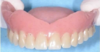

Prothèse amovible complète

Prothèse amovible complète avec polychromie

Prothèse Adjointe Complète